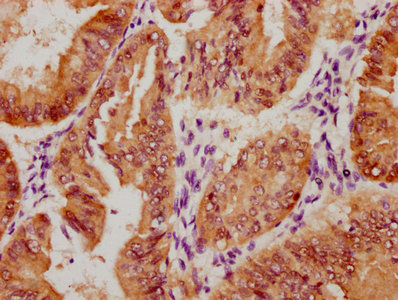

Immunohistochemistry of paraffin-embedded human breast cancer using CSB-PA138304ESR2HU at dilution of 1:100